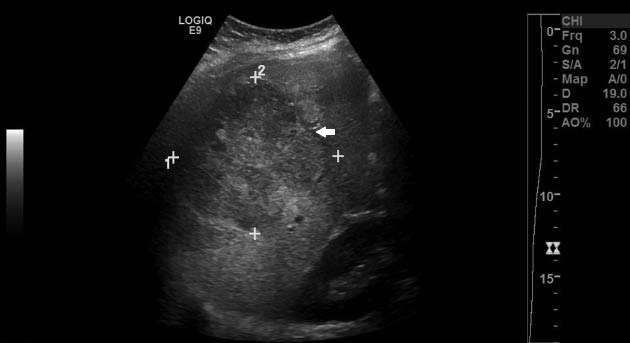

She then represented early in her fourth pregnancy for prenatal care 3 years later. At 8 weeks’ gestation, a baseline abdominal ultrasound demonstrated a 7.3×8.9×8.0 cm asymptomatic liver hemangioma. At 28 weeks’ gestation, she again complained of severe right upper quadrant pain where an abdominal ultrasound showed no interval change in size of the lesion. The patient continued to have abdominal pain requiring increasing narcotic use and frequent hospitalizations for pain control. She received a course of antenatal corticosteroids for fetal lung maturity during admission in which an abdominal ultrasound performed at 32 weeks’ gestation noted expansion of the hemangioma to 10 cm in width (Figure 1). A follow-up MRI confirmed hemangioma growth compared with the size noted on her previous study without evidence of hemorrhage (Figure 2).

Abdominal ultrasound of the maternal liver noting interval increase in size of known right hepatic lobe hemangioma (arrow).